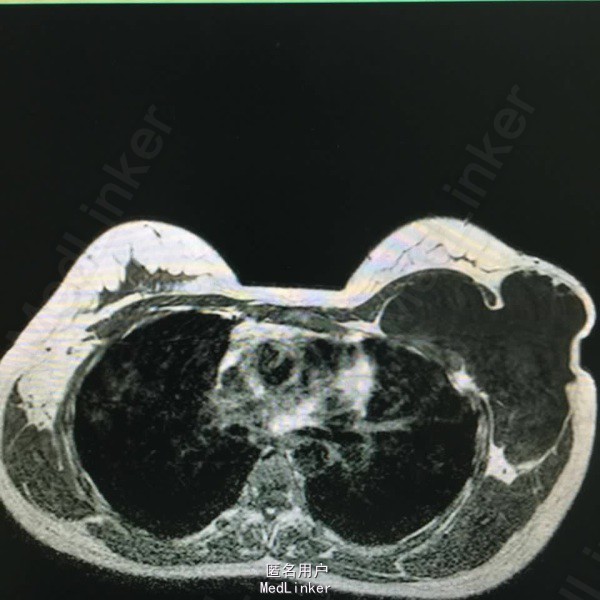

女,28 岁。2年前发现左腋下肿物,近来增大。

左腋下巨大肿物,9厘米。

囊性淋巴管瘤。给予穿刺抽液,注入A组链球菌注射剂。

肿瘤有减小,现一年后为2厘米